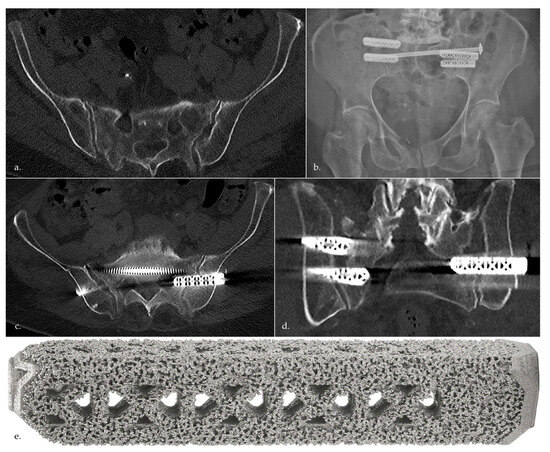

- Bornemann, R.; Pflugmacher, R.; Webler, M.; Koch, E.M.; Dengler, J.; Wirtz, D.C.; Frey, S.P. Clinical Trial to Test the iFuse Implant System(R) in Patients with Sacroiliac Joint Syndrome: One Year Results. Z. Orthop. Unfall. 2016, 154, 601–605. [Google Scholar] [CrossRef]

- MacBarb, R.F.; Lindsey, D.P.; Woods, S.A.; Lalor, P.A.; Gundanna, M.I.; Yerby, S.A. Fortifying the Bone-Implant Interface Part 2: An In Vivo Evaluation of 3D-Printed and TPS-Coated Triangular Implants. Int. J. Spine Surg. 2017, 11, 16. [Google Scholar] [CrossRef]

- Torsional Rigidity of the iFuse Implant in a Sawbones Model Report. SI-BONE Technische Studie, 300191-TS. Available online: https://si-bone.de/anwender/losungen/trauma (accessed on 10 April 2023).